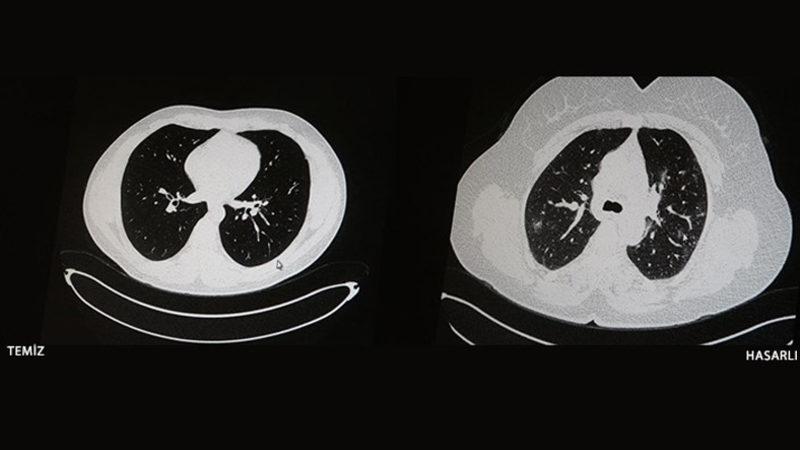

Söz konusu olay, Elazığ'da yaşandı. Öksürük, halsizlik ve yorgunluk gibi belirtilerle hastaneye başvuran iki gencin, aslında COVID-19'a yakalandığı tespit edildi. Bu gençler arasındaki en büyük fark, birinin aşılıyken diğerinin aşılı olmamasıydı. Gençlerin her ikisi için de akciğer tomografisi isteyen doktorlar, aşı olup COVID-19'a yakalanan gencin ciğerlerinde hiçbir sorun tespit edemediler. Aşısız olan genç ise koronavirüsün etkisiyle zatürreye yakalanmıştı.

İşte aşı olan ve olmayan COVID-19 hastalarının tomografi görüntüleri

Konuyla ilgili açıklamalar, Göğüs Hastalıkları Uzmanı Dr. Cebrail Azar tarafından yapıldı. Çekilen tomografi görüntülerinin aşı olmamanın nelere mal olabileceğini gösterdiğini söyleyen Azar, "Ben gencim, benim bağışıklık sistemim kuvvetli." algısına düşülmemesi gerektiğini ifade etti. Herkesin hastalığa yakalanabileceğini ancak önemli olan şeyin hasar olduğunu hatırlatan Cebrail Azar, herkesin aşı olması gerektiğini söyledi.